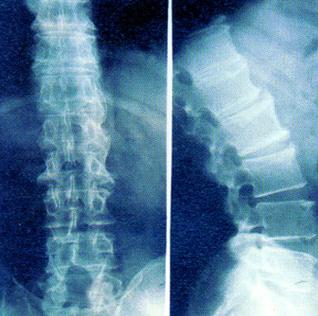

• 成都哪个医院治疗强直性脊柱炎好

当患上强直性脊柱炎后,患者首先要做的就是到医院接受检查并治疗 ...

• 华西专业的治疗强直性脊柱炎专科医院

越来越多的年轻人患上强直性脊柱炎,强直性脊柱炎已经不是老年人 ...

• 成都哪家医院治疗强直性脊柱炎好

很多年轻朋友们都曾问,自己还真么年轻怎么就会患上了强直了呢, ...